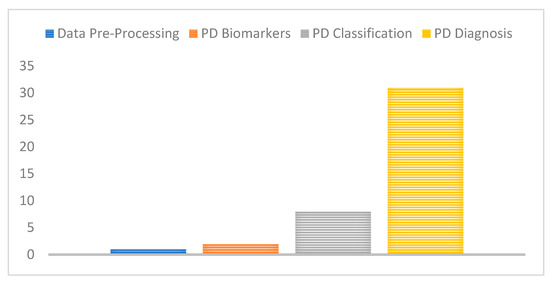

As shown in Figure 9, it is clear that most of the related work invested in the detection of PD or classification of subjects into PD and healthy controls. Few works have addressed the identification of PD biomarkers as well as classification of PD into one of the five stages which have significant clinical implications and help further support the clinical diagnosis and progression monitoring of the disease.

Figure 9.

Number of studies for each PD challenge considered.